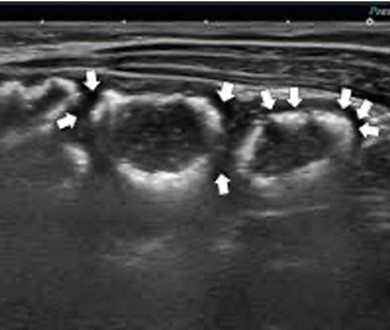

| Bowel wall thickening/thinning | |

| Strengths | Considerations |

|

![]() |

| Thickened loop of small bowel (0.35 cm) | Thinning of colonic wall |